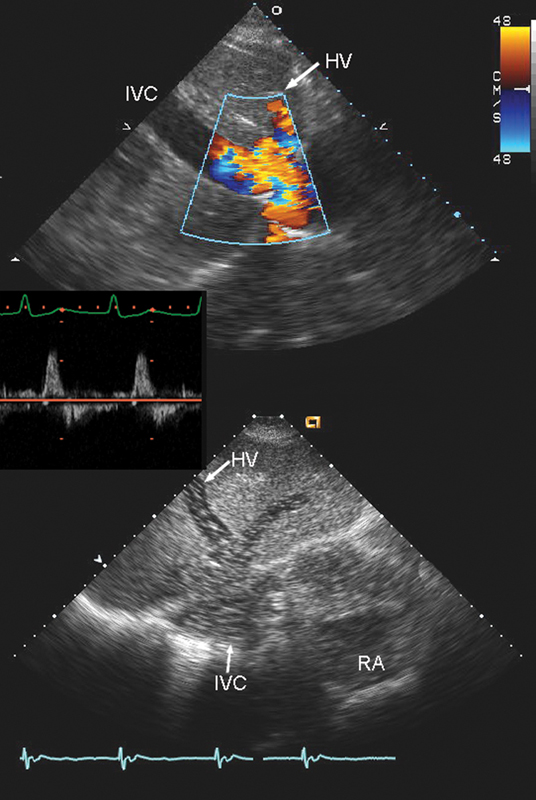

فحوصات تشخيصية لبعض امراض القلب والشرايين التاجية